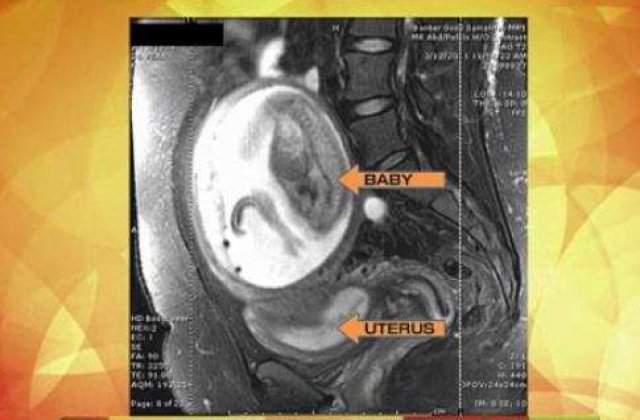

Nicky Soto, in varsta de 27 de ani, a aflat in a 18-a saptamana de sarcina ca va avea un baietel, insa medici nu au putut stabili cu precizie unde se dezvolta copilul. Tanara a fost avertizata ca daca placenta ar fi fost atasata de unul dintre organele vitale, i-ar fi putut fi fatal, scrie Huffington Post.

Insa, potrivit MSNBC, aceasta a decis sa pastreze sarcina si sa-i fie monitorizata indeaproape, din spital, desi atat viata ei cat si a copilului era in pericol. Dupa 32 de saptamani de sarcina ectopica, femeia a dat nastere unui baietel perfect sanatos.

Sarcina ectopica sau sarcina extrauterina inseamna ca ovulul fertilizat este implantat in exteriorul uterului, in general intr-unul dintre tuburile falopiene. De obicei se recurge la avort, riscurile de deces pentru mama fiind foarte mari.

Azelan Cruz Perfecto a venit pe lume sanatos, la sectia de Cezariana a Centrului Bunul Samaritean din Phoenix, Arizona, iar medicii spun ca este un caz unic, o minune.